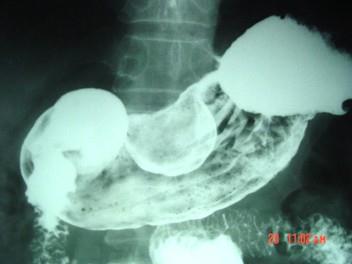

男,52岁,中上腹痛,影像检查如图,最可能的诊断是()A.慢肥厚性胃炎B.胃癌C.胃溃疡D.胃平滑肌瘤E.胃平滑肌肉瘤

问题 男,52岁,中上腹痛,影像检查如图,最可能的诊断是()

选项 A.慢肥厚性胃炎 B.胃癌 C.胃溃疡 D.胃平滑肌瘤 E.胃平滑肌肉瘤

答案 D